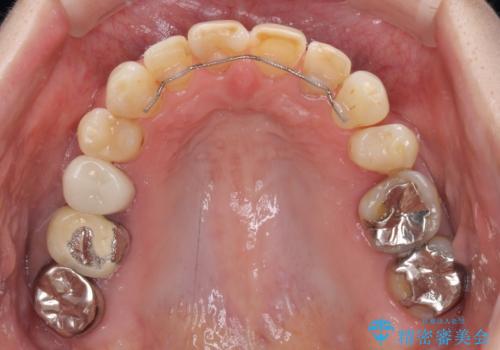

以前矯正治療をされ、その時には歯列が整ったので満足されたそうですが、若干の後戻りにより隙間ができ、矯正治療前に治療していた虫歯の跡が気になったため、オールセラミックによる審美治療を希望されました。

目立つ範囲である前歯4歯をオールセラミッククラウンにて補綴することとしました。